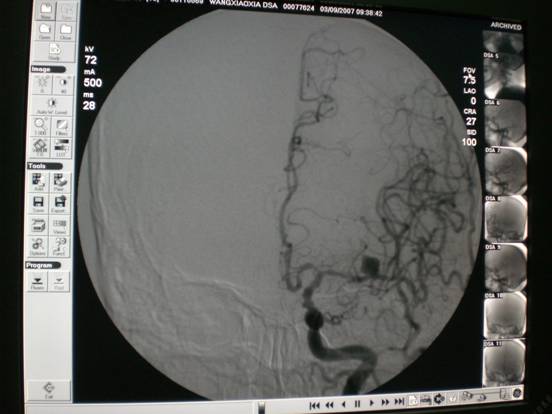

脑血管造影不但能清楚地显示颈内动脉、椎基底动脉、颅内大血管及大脑半球的血管图像,还可测定动脉的血流量,所以,目前已被广泛应用于脑血管病的检查,特别是对于动脉瘤、动静脉畸形等定性定位诊断,其不但能提供病变的确切部位,而且对病变的范围及严重程度亦可清楚地了解,为手术治疗提供可靠的客观依据。另外,对于缺血性脑血管病,也有较高的诊断价值,DSA可清楚地显示动脉管腔狭窄、闭塞、侧支循环建立情况等,特别对静脉系统血栓形成提供可靠的诊断依据。对于脑出血、蛛网膜下腔出血,可进一步查明导致出血的病因,如动脉瘤、血管畸形、海绵状血管瘤等。总之,全脑血管造影是诊断脑血管病的金标准。

颅内动脉瘤